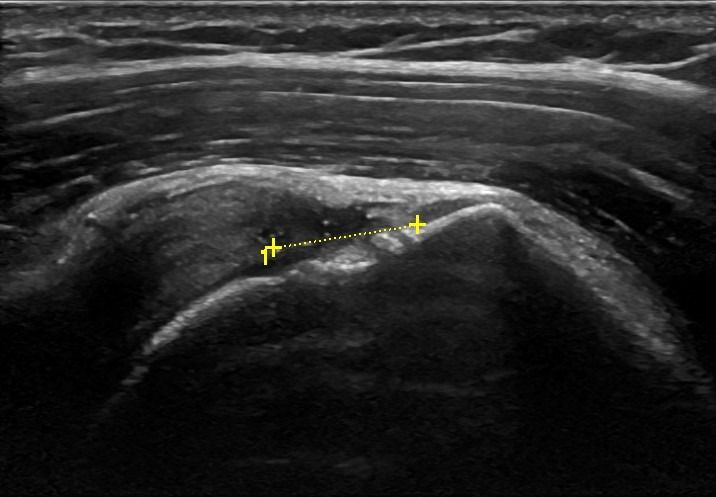

- Ασβεστοποιός Τενοντίτιδα